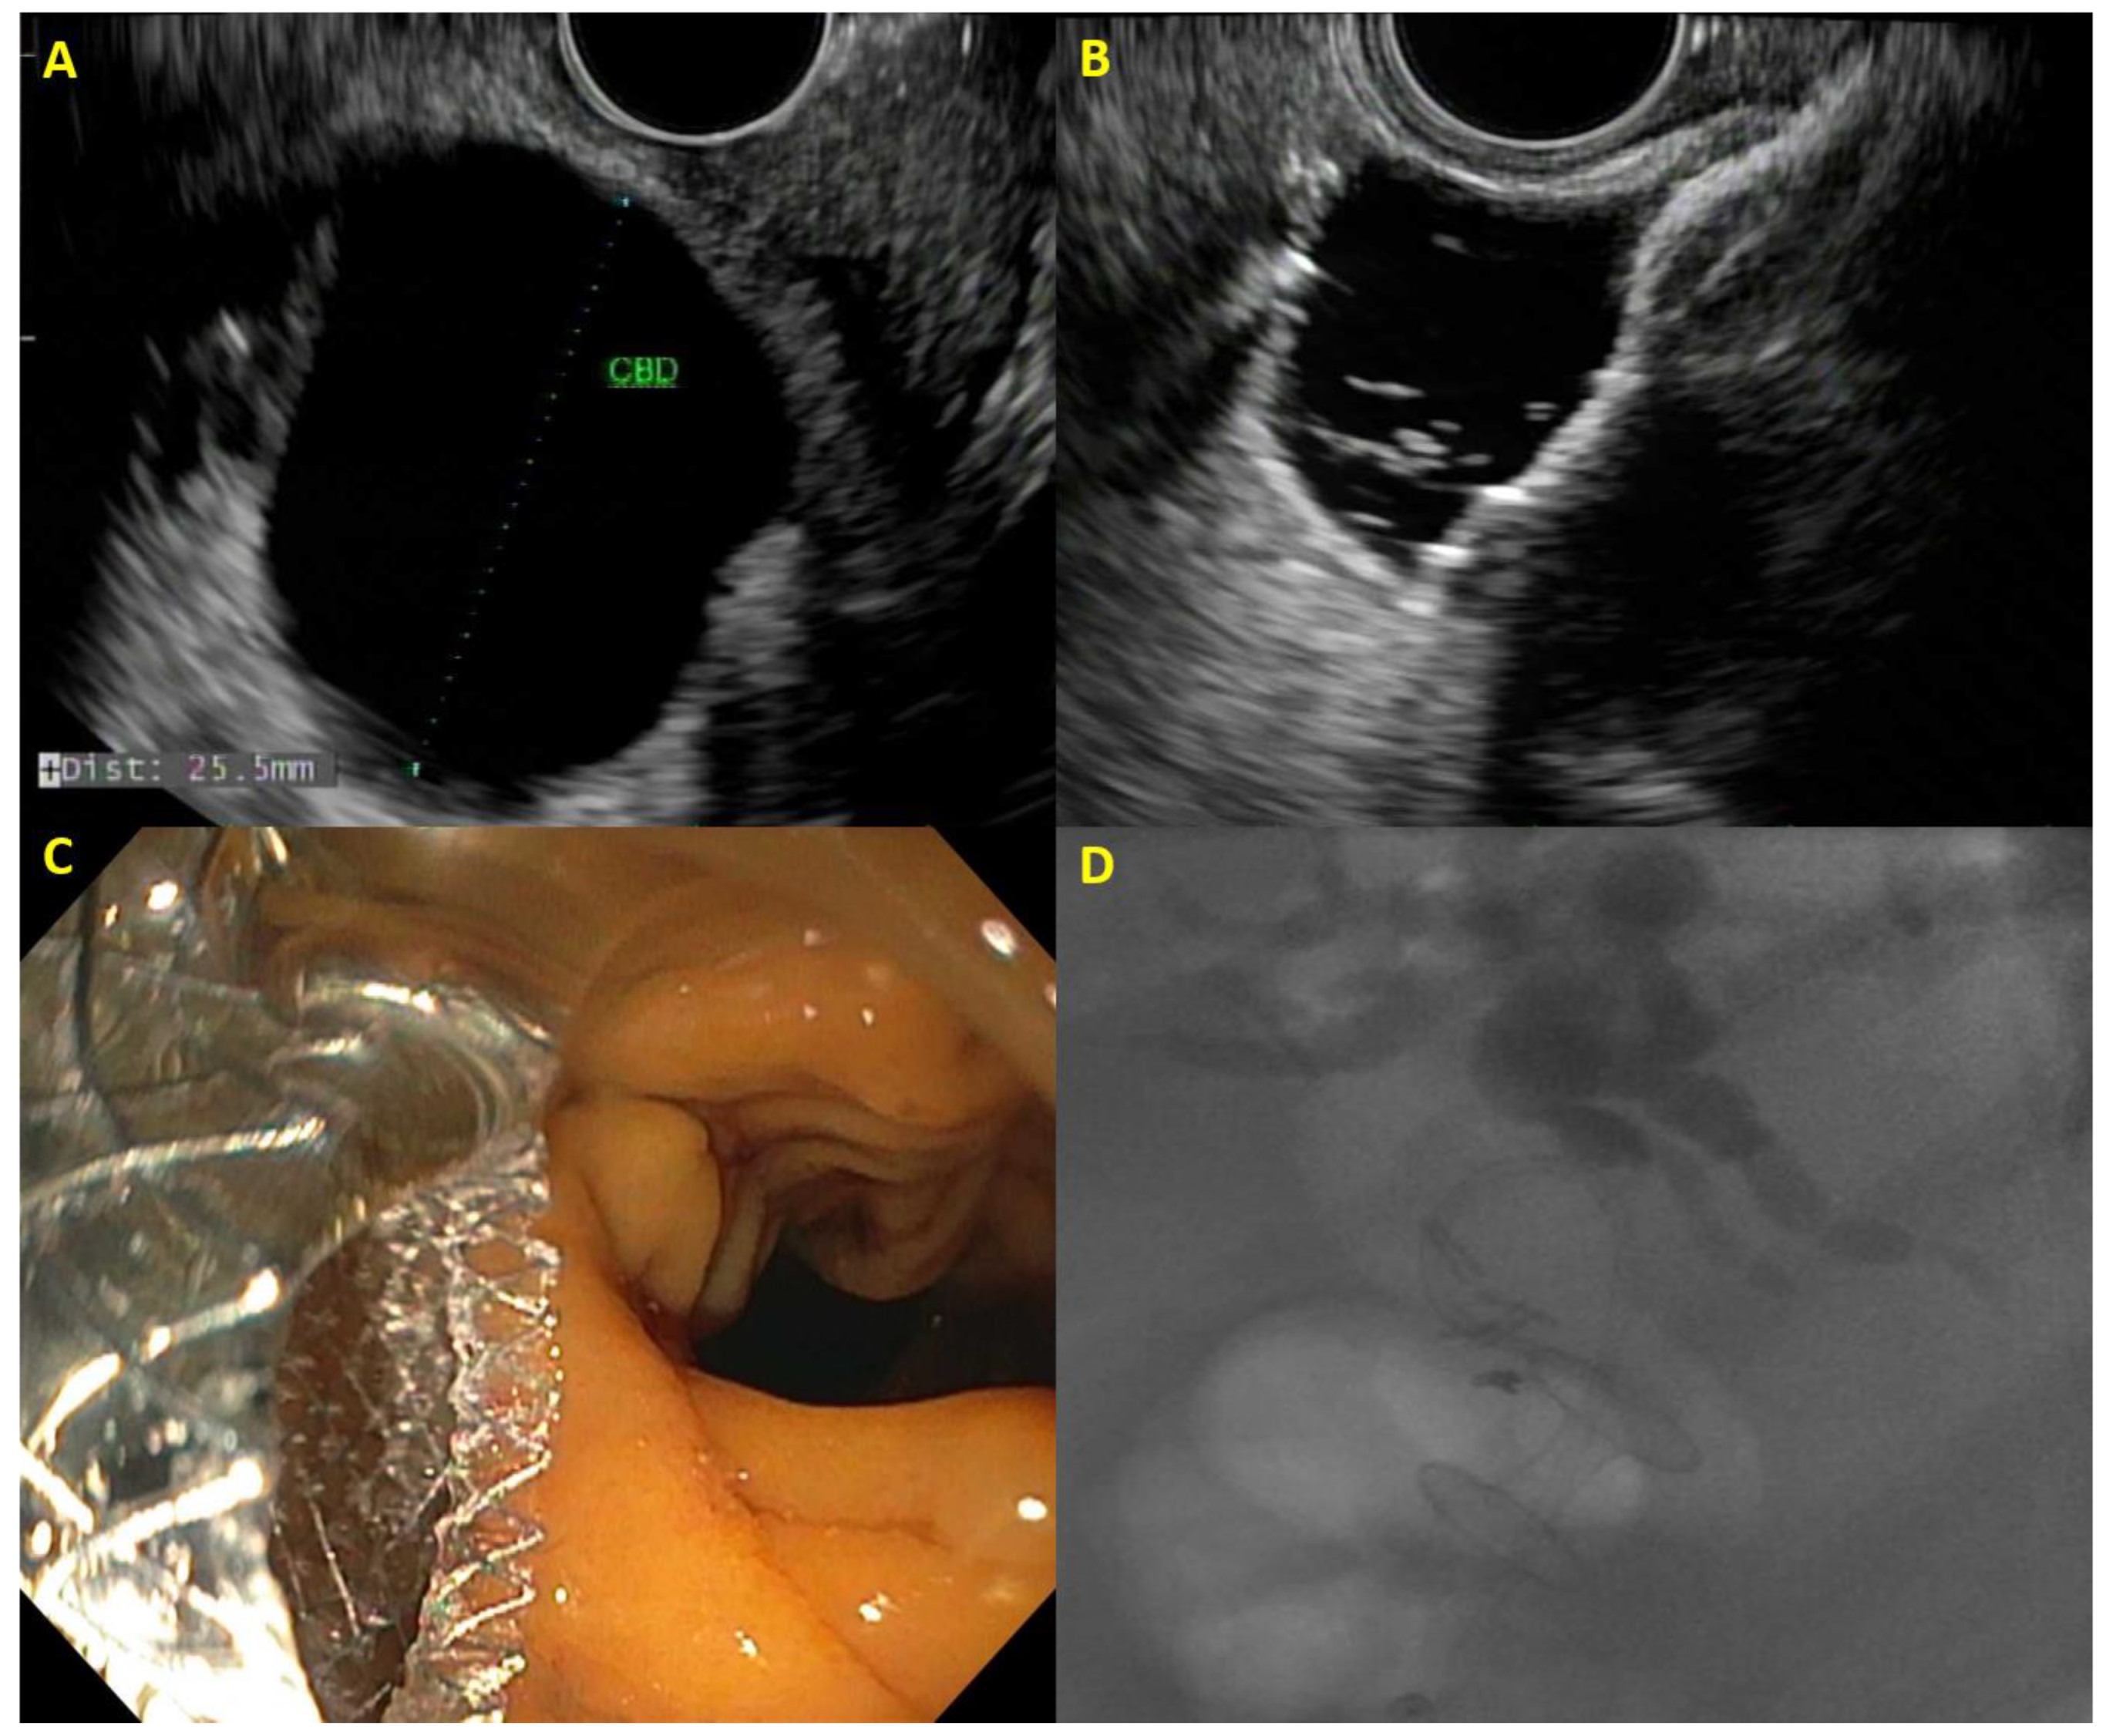

While there is currently no evidence-based algorithm for biliary drainage, at our center, we follow a multidisciplinary approach to patients with PDAC-related biliary obstruction that incorporates patient anatomy and cancer stage (Figure 2).

Figure 2. Algorithm for biliary drainage for patients with pancreatic cancer.